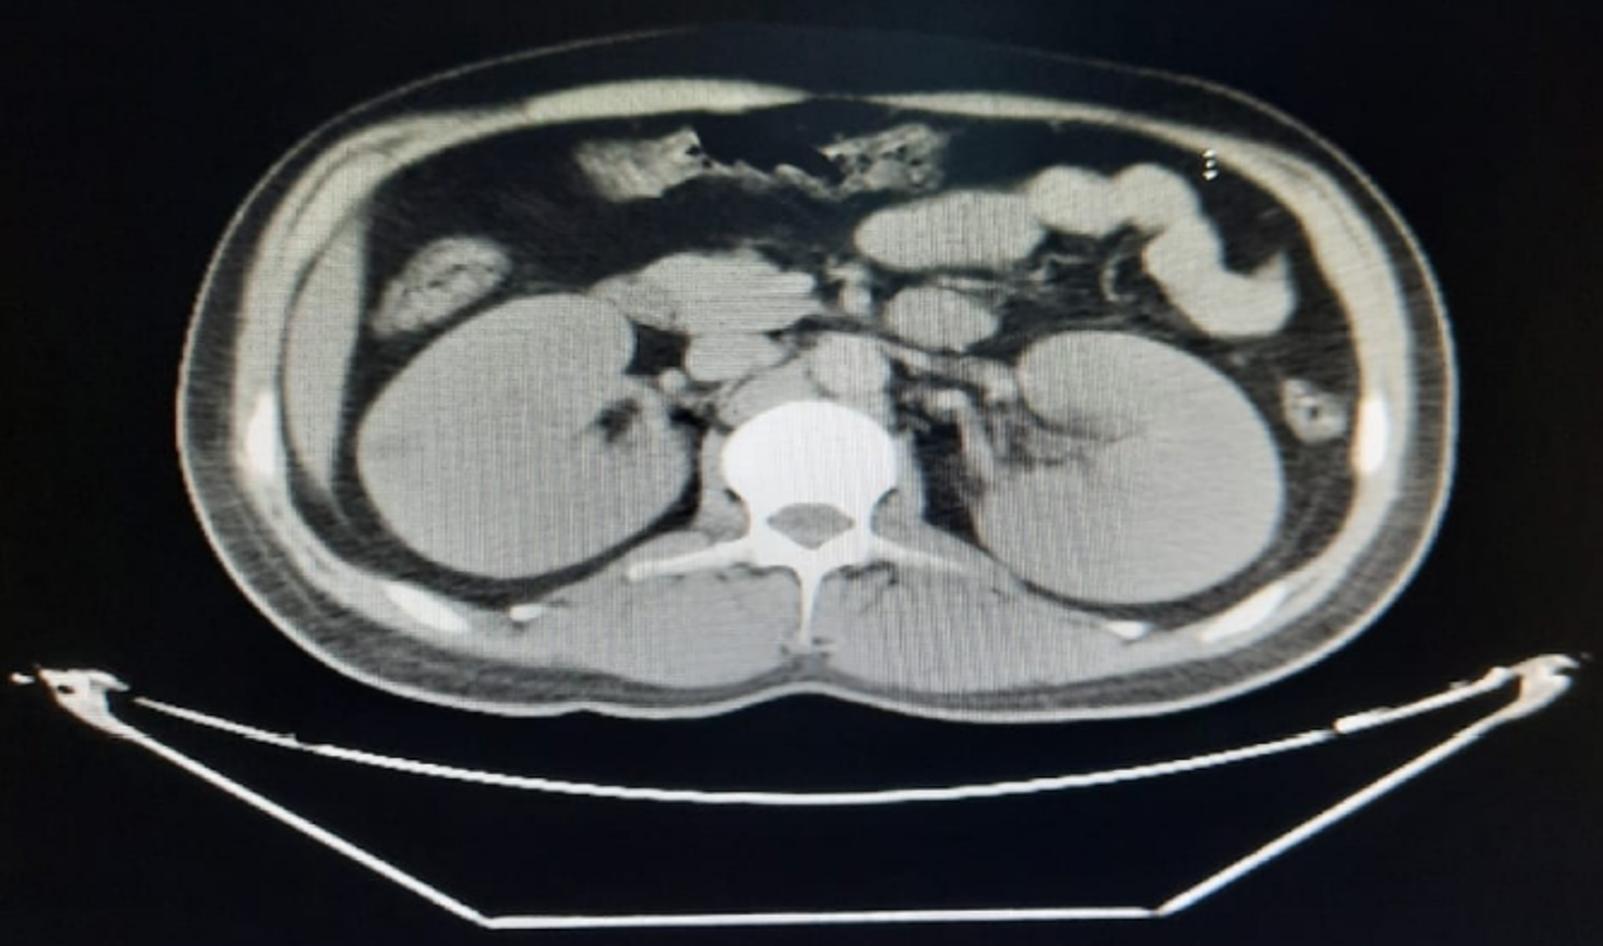

CT Abdomen with contrast was done and ruled out pancreatitis, but bilateral almost symmetrical nephromegaly were very evident (Figure 1).

Glycogen accumulation in liver and kidneys may lead to hepatic adenomas and nephromegaly up to renal failure.